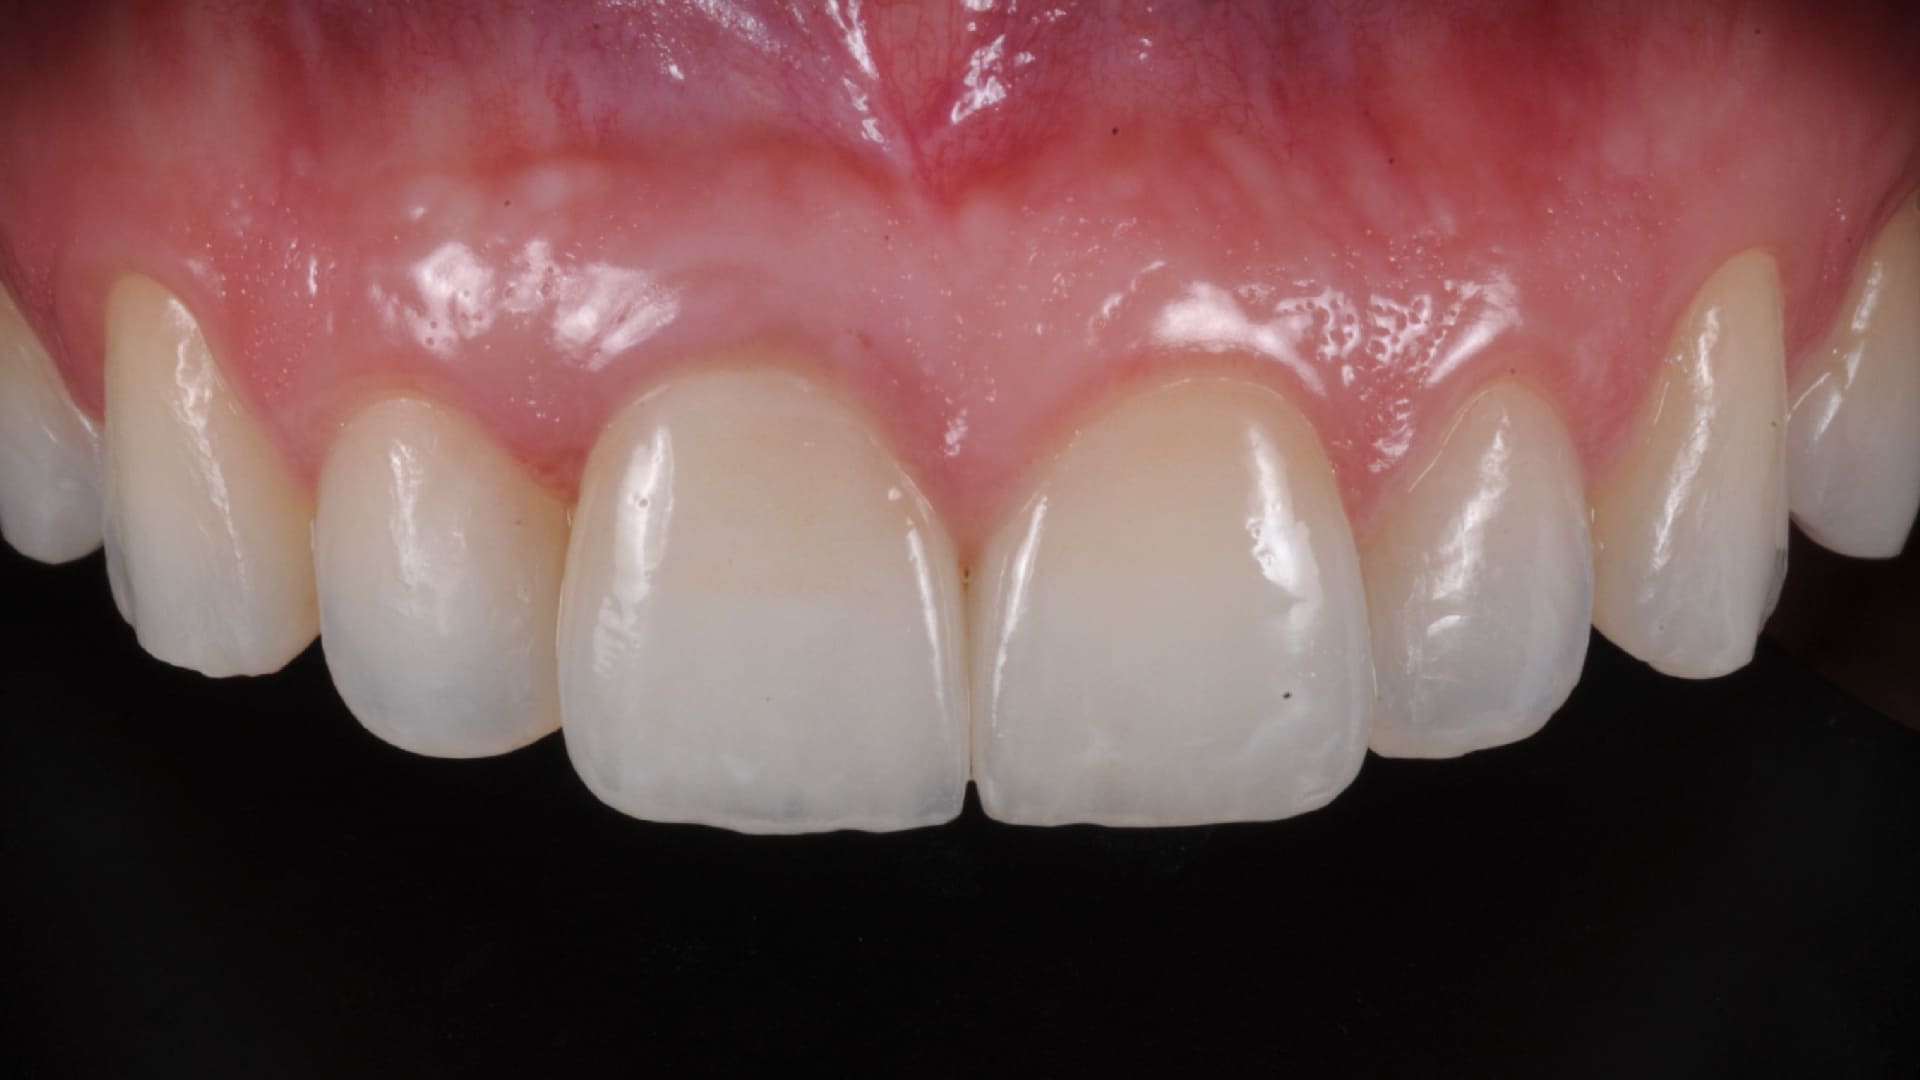

CLINICAL CASES